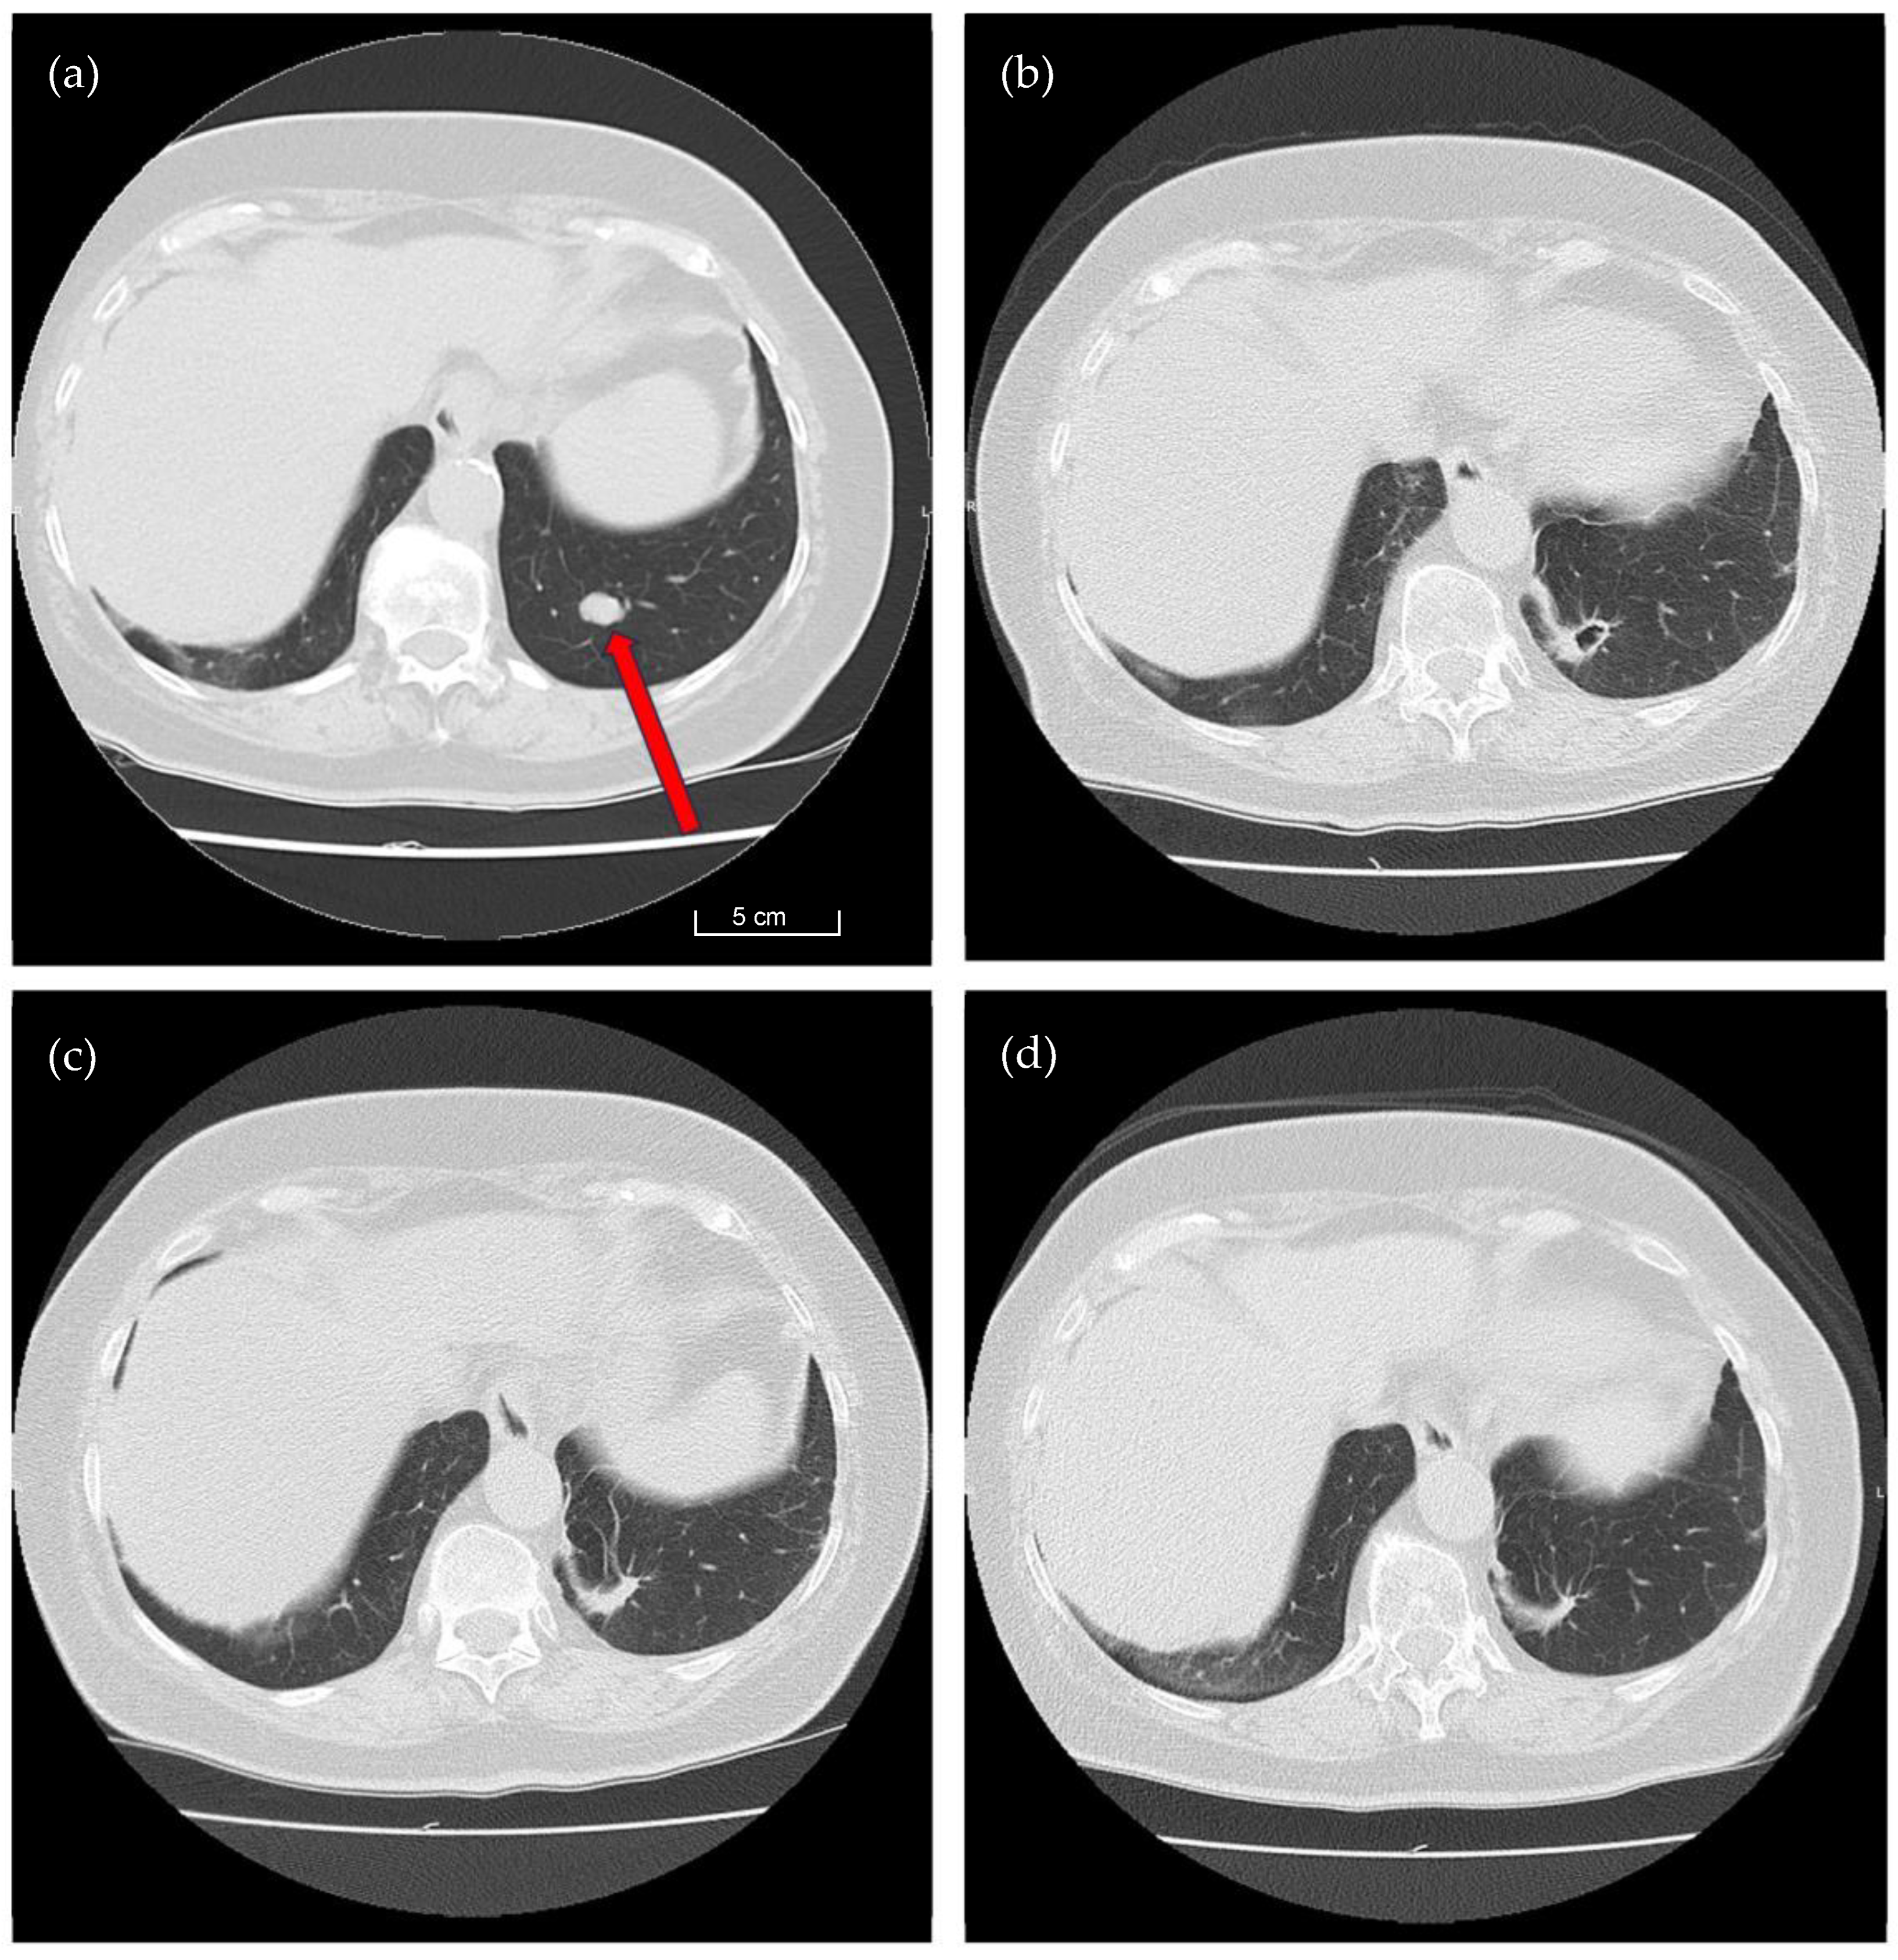

Following an expected immediate loss of lung function, recovery occurs gradually. Our findings demonstrate that lung function fully recuperates over the long term following open resection of unilateral solitary or multiple metastases, regardless of whether the metastases were centrally or peripherally located. By utilizing the 1318 nm laser, we are ultimately able to preserve a maximum amount of lung tissue since the resection takes place very close to the surface of the metastasis. See Figure 3, which offers a series of illustrative CT images capturing the tissue recovery throughout the postoperative course.

Figure 3. CT Findings Prior and After Laser-Assisted Pulmonary Metastasectomy. This set of four CT images illustrates the longitudinal course of pulmonary metastasectomy in a 74-year-old female patient diagnosed with two metastases of renal cell carcinoma in the left lung. The images provide a comprehensive view of postoperative changes over a period of one year. (a): this CT scan was captured four weeks before the laser-assisted metastasectomy. It displays a distinct metastatic lesion measuring approximately 12 mm in Segment 10 of the left lung (red arrow). (b): three months after the surgical procedure, Image b reveals significant changes in the left lung. A characteristic air-filled cavity resulting from laser ablation is clearly visible in Segment 10. (c): Six months post-surgery, the previously formed pulmonary cavity has completely resolved, leaving only residual scar tissue at the resection site. (d): a CT scan captured 12 months postoperatively shows further regression. The residual scar tissue in Segment 10 continues to diminish, demonstrating gradual but progressive recovery.